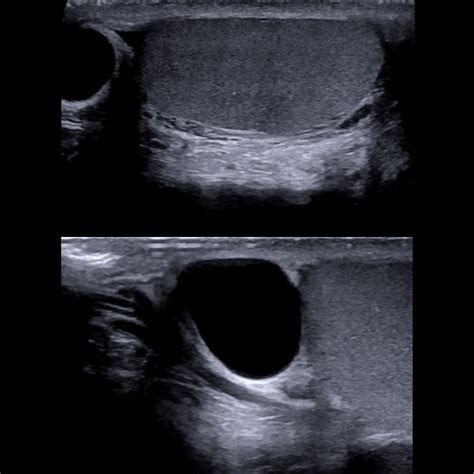

An ultrasound allows the physician to clearly distinguish between a solid mass—which requires further investigation—and a fluid-filled cyst, which is typically benign. If you have been looking for Testicular Cyst Images, you have likely seen ultrasound depictions showing dark, well-defined areas; these represent the fluid within the cyst, contrasting with the more textured appearance of the testicle itself.